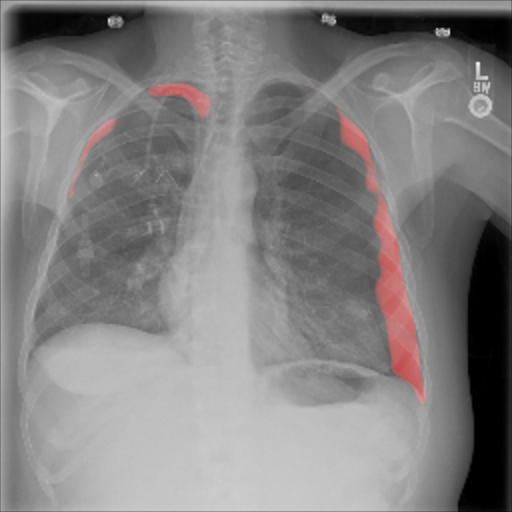

The pre-trained ResNet-50 was also employed as the patch-level classifier within the MIL approach. We chose the binary cross-entropy between the maximum patch score and the image-level label as the loss function. The batch size was selected as the number of patches per image. We trained with an initial LR of for 30 epochs and achieved an average AUC of 0.930.01 using this method. High patch scores (indicated by thicker red frames, cf. Fig. 5(c)) give a hint on the location of the pneumothorax.